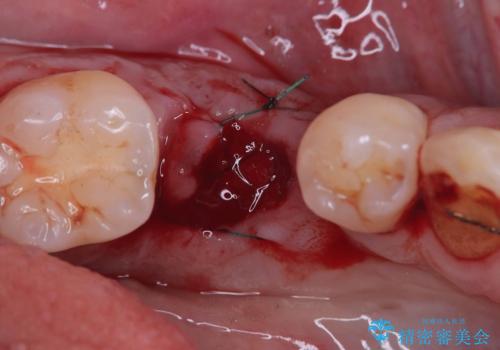

インプラントを抜去後、再びインプラントで治療を行いました。

当法人はどんなインプラントでも簡単に除去する事ができ、痛みが少なくインプラントを埋入する事ができます。

当患者様もインプラントのオペ後痛みが全くなく痛み止めも1錠も飲まず驚かれていました。